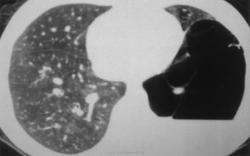

К первой группе признаков относится наличие в области аномалии характерного ячеистого легочного рисунка, являющегося отражением множественных тонкостенных воздушных полостей. Наиболее часто ячеистый рисунок при кистозной гипоплазии наблюдается в области верхней доли правого легкого или же занимает все левое легкое.

Ячеистый рисунок отмечается практически у всех больных кистозной гипоплазией легких. Таким образом, на основании обзорных рентгенограмм можно лишь заподозрить наличие кистозной гипоплазии легкого, главным образом при наличии ячеистого легочного рисунка, разумеется, с учетом соответствующих клинических данных.

Томографическоеисследование позволяет получить более четкое представление о наличии в легком множественных тонкостенных полостей. Дифференциально-диагностическое значение этого метода ограничено.

Бронхография. Для уточнения диагноза всем больным показана двусторонняя бронхография.Бронхографическая картина кистозной гипоплазии характерна. Крупные бронхи в зоне определенного по обзорным рентгенограммам ячеистого легочного рисунка вплоть до субсегментарных ветвей в большинстве случаев имеют нормальный вид, но обычно несколько сближены. Дистальнее их в зоне поражения выявляются множественные, наслаивающиеся одна на другую тонкостенные полости различного диаметра, частично или целиком заполненные контрастным веществом.